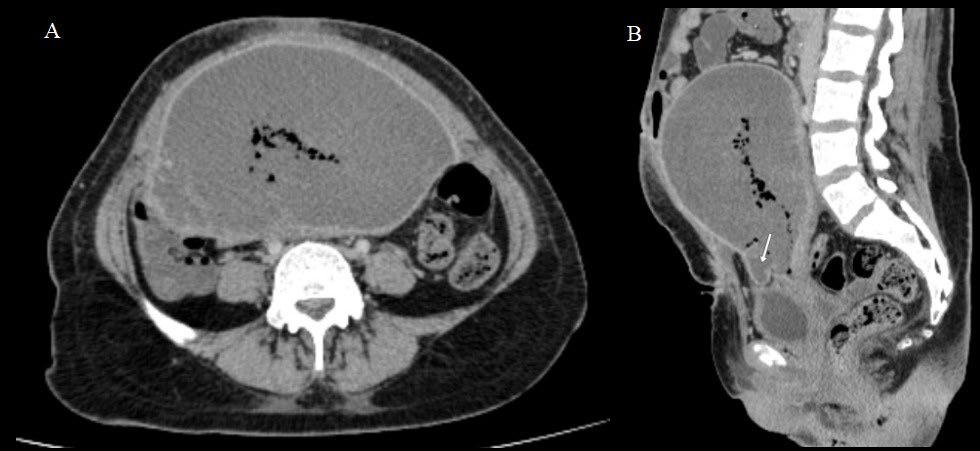

Therefore, having preoperative knowledge of the likelihood of recurrence would assist in selecting the most suitable liver transplant recipients, potentially avoiding unnecessary surgeries, and improving patient prognosis and organ allocation. In this context, radiomics, which involves high-throughput data extraction from medical images, holds great promise.3 However, there is ongoing debate regarding the optimal data selection strategy, as factors such as the choice of contrast phase and volume of interest (VOI) can significantly impact radiomic analysis results.4-6 Therefore, the authors’ study aimed to investigate how these factors influence radiomic features (RF), to identify the optimal combination for predicting HCC recurrence in liver transplant candidates.

Segmentation Feature Selection Modelling Arterial phase Portal venous phase Delayed phase = Nodule = +5 mm (PT_5) = +10 mm (PT_10) = +15 mm (PT_15) = Background Nodule AP-PVP PVP-DP AP-DP 0% 0% 20% 20% 40% 40% 60% 60% 80% 80% 100% InterVOI MRC >10% Interphase MRC >10% 100% PT_5 PT_10 PT_15 AUC (CI: 95%) P value Pseudo-R2 No. of RFs AP_Nodule 0.77 (0.65–0.90) 0.020 0.23–0.32 8 AP_PT_5 0.90 (0.83–0.97) <0.001 0.33–0.44 8 AP_PT_15 0.88 (0.76–1.00) <0.001 0.36–0.46 12 AP_Nodule_Norm 0.87 (0.75–0.98) <0.001 0.34–0.44 9 DP_Nodule_Norm 0.86 (0.77–0.95) <0.001 0.24–0.35 11 AP_PT_5_Norm 0.88 (0.80–0.97) <0.001 0.31–0.44 8 PVP_PT_10_Norm 0.88 (0.77–0.99) <0.001 0.35–0.45 8 PVP_PT_15_Norm 0.77 (0.65–0.89) 0.002 0.13–0.24 5

Figure 1: Workflow and results from the radiomic analysis of hepatocellular carcinoma nodules and peritumoural regions extracted from the waitlist placement CT scans of liver transplant candidates to predict disease recurrence.

across arterial, venous, and delayed phases, with or without peritumoral region of 5, 10, and 15 mm. An area of ‘background’ liver parenchyma, distant from the lesions, was also segmented in each phase.

A total of 107 RFs, both directly extracted from segmentations, and normalised for the ‘background’ parenchyma, were obtained using PyRadiomics (Python Software Foundation, Beaverton, Oregon, USA). The normalisation was conducted by calculating the ratio between the RFs extracted from the VOI, and those extracted from the background segmentation. These features were then compared with each other for inter-VOIs and inter-phase relative change, while autocorrelation was assessed using Spearman’s rank correlation coefficient. RFs with relative change <10% and rank correlation coefficient >0.90 were considered non-informative. Informative RFs with different distribution in patients with and without posttransplant recurrence were selected to build multiple logistic regression models. Prediction of post-transplant recurrence was assessed by comparing the areas under the curve from receiver operating characteristic analysis and goodness-of-fit, expressed as the value range of Tjur’s, McFadden’s, and Nagelkerke’s R2 .

RESULTS

The CT scans of 53 patients were selected, resulting in a total of 1,032 segmentations from 86 nodules, with eight (15%) recurrence cases. When varying VOIs and phases, the proportion of noninformative RFs, indicating insignificant differences between the VOI and liver background, were 14–26% and 16–34%, respectively, while 4% of RFs showed autocorrelation >0.90.

The selected informative RFs allowed the building of eight predictive models with adequate performance and goodness-of-fit,

each comprising 5–12 RFs, with an area under the curve of 0.77–0.90 (p<0.02) and pseudo-R2 values of 0.13–0.46. A predominance of models derived from the arterial phase was observed, utilising the nodule with or without a 5 mm peritumoral region as the VOI, followed by the venous phase, including a 10–15 mm margin after normalisation (Figure 1).

CONCLUSION

Selection of optimal VOI and contrast phase combination is critical to maximise post-liver transplant HCC recurrence prediction using quantitative CT imaging. Specifically, segmenting the nodule, eventually including a 5 mm peritumoral region, during the arterial phase, or the nodule with a 10-15 mm margin during the venous phase after normalisation against the liver background, appeared to be the most promising strategy.●